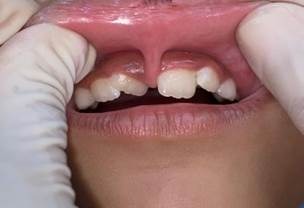

Figura 2: Fotografia inicial realizada no primeiro atendimento

Figura 1: A radiografia panorâmica mostra o mal posicionamento dos incisivos centrais pela inserção anômala do freio labial superior

Na avaliação intraoral e de radiografia panorâmica, observou-se que havia espaçamento entre os dentes 11 e 21, mordida cruzada anterior, apinhamento dentário, dentição mista e uma inserção alta do frênulo labial superior estendendo-se para a região interincisal palatina. Anotadas as informações, fez-se o registro fotográfico autorizado e houve uma conversa com a criança, onde foi explicado a ela a importância do procedimento e como ele seria feito. Foi dito a ela que não ia sangrar, seu rosto não ficaria inchado, não doeria e a cicatrização seria mais rápida do que fazendo a cirurgia tradicional com bisturi. A menina, demonstrando aceitação, foi-lhe entregue um brinquedo como reforço positivo e ela foi liberada junto com os pais, tendo o retorno agendado para a realização da cirurgia.